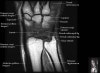

- Axial section

Axial PD fat suppressed evaluates the tendons of the wrist and carpal tunnel, including the median nerve.